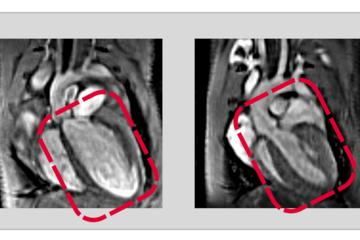

Über ein eindrucksvolles Beispiel dieser Forschung referierte Dr. Pieterjan Dierickx, Leiter einer Forschungsgruppe am MPI. Zusammen mit seinem Team widmet er sich den Auswirkungen der Inneren Uhr auf die Entstehung von Herz-Kreislauf-Erkrankungen. So sei es kein Zufall, sondern eine Folge der auch als zirkadiane Rhythmik bezeichneten Inneren Uhr, dass Herzinfarkte oft in den frühen Morgenstunden entstünden. „Dahinter liegen komplexe genetische Abläufe, die wir verstehen möchten. Fernziel ist, die Innere Uhr so zu beeinflussen, dass weniger Erkrankungen durch sie ausgelöst werden“, erklärte Dierickx.